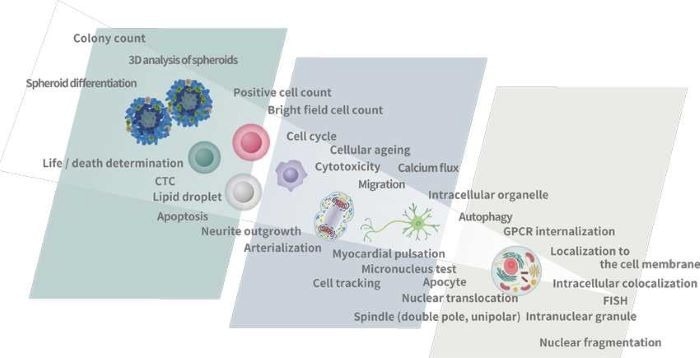

Applications

Image Credit: Yokogawa Life Science

A variety of optional functions enable various analyses

The Basic Pack offers the fundamental functions to extract quantitative data on cell shape and brightness from fluorescence images. Furthermore, a range of analyses that are not possible with the basic pack become achievable by adding extra functions.